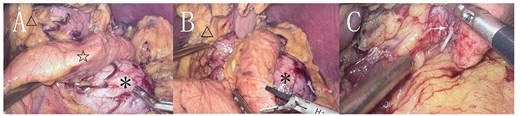

During surgery, a lump was identified behind the tail of the pancreatic body, with no apparent adhesion or invasion of the surrounding area. The pancreatic tail was completely freed and suspended along with the splenic artery and vein, revealing that the mass originated from the lesser curvature of the stomach (Fig. 2). After fully dissociating the mass, the gastric tissue was separated from it along the lesser curvature, and the mass was completely removed from the surface of the left renal vein. The mass, visible to the naked eye, measured approximately 5 × 6 cm (Fig. 3), and yellow viscous content was observed upon incision. Postoperative pathological examination revealed a retroperitoneal mass. The fibrous cyst wall tissue was lined with ciliated columnar epithelium, with numerous foam cells and lymphocyte infiltration, suggesting a diagnosis of bronchogenic cyst (Fig. 3). The postoperative diagnosis included gastric bronchogenic cyst, gallbladder stones with chronic cholecystitis, and coronary atherosclerotic heart disease. The patient received postoperative symptomatic treatment, including antiinfection therapy and fluid replacement. A follow-up abdominal CT scan six days after surgery showed no obvious residual cysts (Fig. 1C), and the patient was discharged.

Cyst (*), pancreas (☆), lesser curvature of the stomach (△). A: The cyst originates from the lesser curvature of the stomach, located posterior to the pancreas. B: The cyst is adjacent to the lesser curvature of the stomach. C: The cyst after separation from the surrounding tissue (→ indicating the broken end).